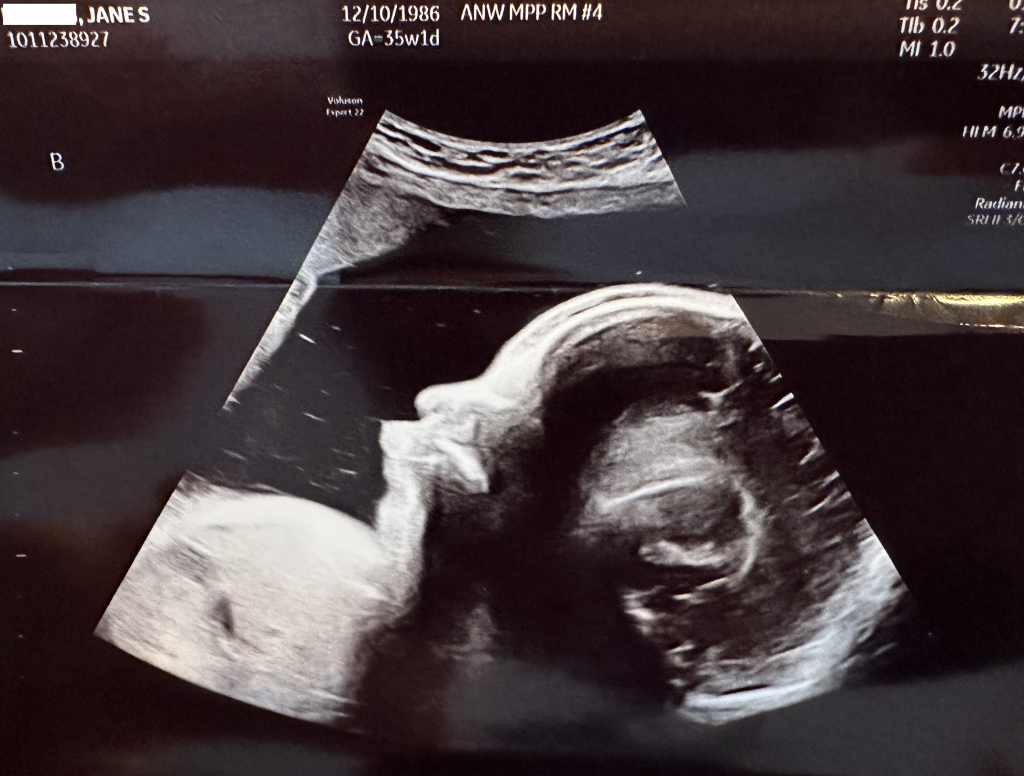

The entire team at Children’s has been more than amazing to work with and we just had our weekly checkup with them today. We are at 35 weeks and 1 day today, Luna is weighing in at 5lbs 6oz and Leo is at 6lbs 0oz, both doing great and on track for growth! Luna is still breech, but today Leo was cephalic… Jane has mentioned they both have been very very active at night, so there is still a chance Luna could flip around yet. Just in case, they had us schedule our C-section today which would take place on Feb 15th in the event they don’t come earlier.